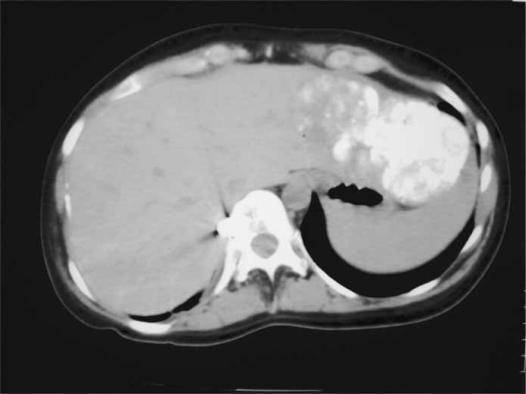

A 25-year-old Caucasian woman (gravida 1, para 1) presented with a painful epigastric mass 1 day after normal vaginal delivery of a 3.8-kg term infant. She had experienced abdominal discomfort for about 2 weeks before delivery. Four days post-partum, she underwent operation for the epigastric mass, which was thought to be a hernia. A transverse incision was made in the epigastrium, and a large tumour measuring 10 cm in diameter was found arising from the left lobe of the liver. There was no evidence of cirrhosis. An incision biopsy of the tumour was taken, the histology of which later showed HCC of fibrolamellar type. The patient was then transferred to this unit. Subsequent blood tests revealed a mildly elevated alpha-fetoprotein (AFP) of 40.5 IU/ml (consistent with 1 week post-partum) and other tumour markers (CEA, Ca 125, Ca 19.9) were within the normal range. Serology for hepatitis B and C was also negative. No metastases were detected on a bone scan or computed tomography (CT) of the chest, and unifocal disease was established with a Lipiodol-enhanced CT (Figure 1).

Figure 1. .

Upiodol-enhanced CT scan showing a solitary tumour in the left lateral segment of the liver (arrow).